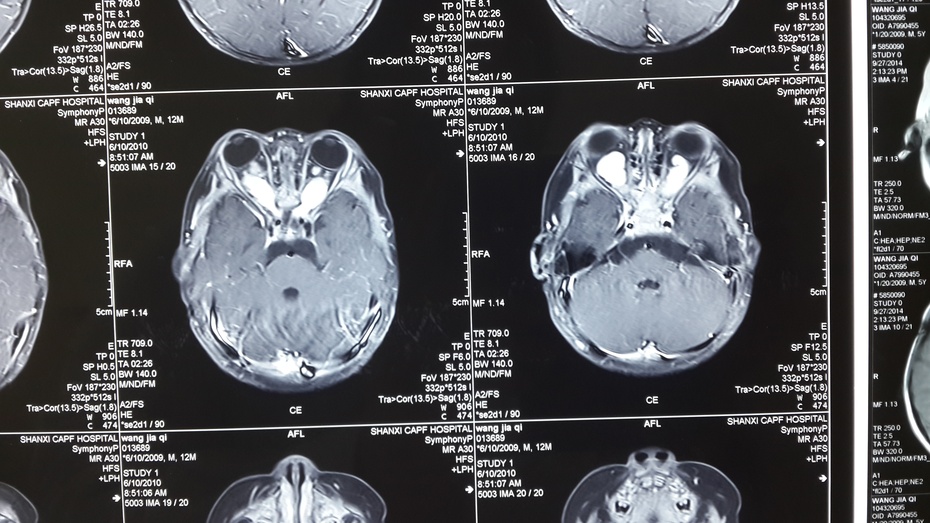

贺教授检查,发现孩子大大的眼睛,红红的脸颊,亮黑但显得较大的瞳仁。孩子头颅MRI增强扫描显示:双侧视神经增粗、视交叉成结节状。诊断:视神经胶质瘤。是神经胶质瘤因该如何治疗呢?!